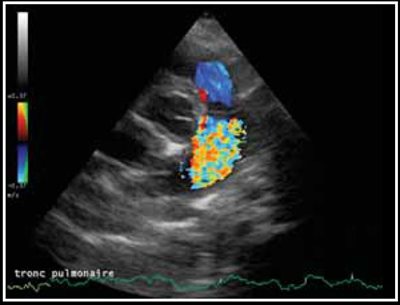

Photo 2 - Persistance du canal artériel, mode Doppler couleur sur une vue crâniale par abord parasternal gauche.

Le canal artériel est visualisé dans 96 % des cas en mode bidimensionnel ou en mode Doppler couleur sur une coupe petit axe transaortique par abord parasternal droit (Photo 1), sur une coupe petit axe par abord parasternal crânial gauche (Photo 2), ou plus facilement sur une coupe longitudinale des gros vaisseaux (aorte et tronc pulmonaire) par abord parasternal crânial et dorsal gauche (Photo 3).

Dans la majorité des cas des turbulences importantes sont visibles dans le tronc pulmonaire (Photo 4) [1,2].